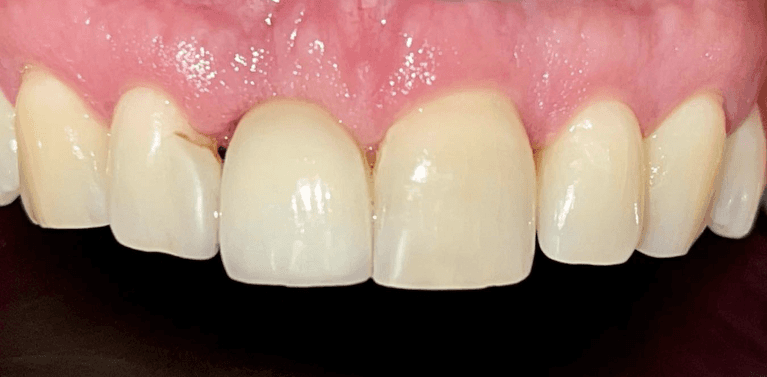

Broken Upper Central incisor with root canal replaced with Immediate implant after extraction.